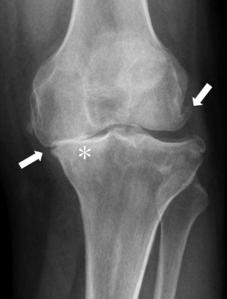

First, your doctor may tell you that you have this. They may take an x-ray of your knee joint, or they may diagnose you based off asking you a few questions.

Whether you are walking, running, climbing stairs, or getting out of a chair, your knee joint has to be able to support your entire body weight and move freely. It is able to do this because the bones which support your body weight are coated in an incredibly smooth, shock absorbing tissue called cartilage (if you want to learn more about this and other structures of the knee joint, click here). However, once you begin to develop osteoarthritis, this incredible cartilage begins to break down, become rough, and wear away. Over time, this breakdown will progress to a point where instead of supporting your body weight on a smooth cushion (your cartilage), you will be supporting your body weight on the rough ends of your bones. This is what your doctor means when they say “bone-on-bone”